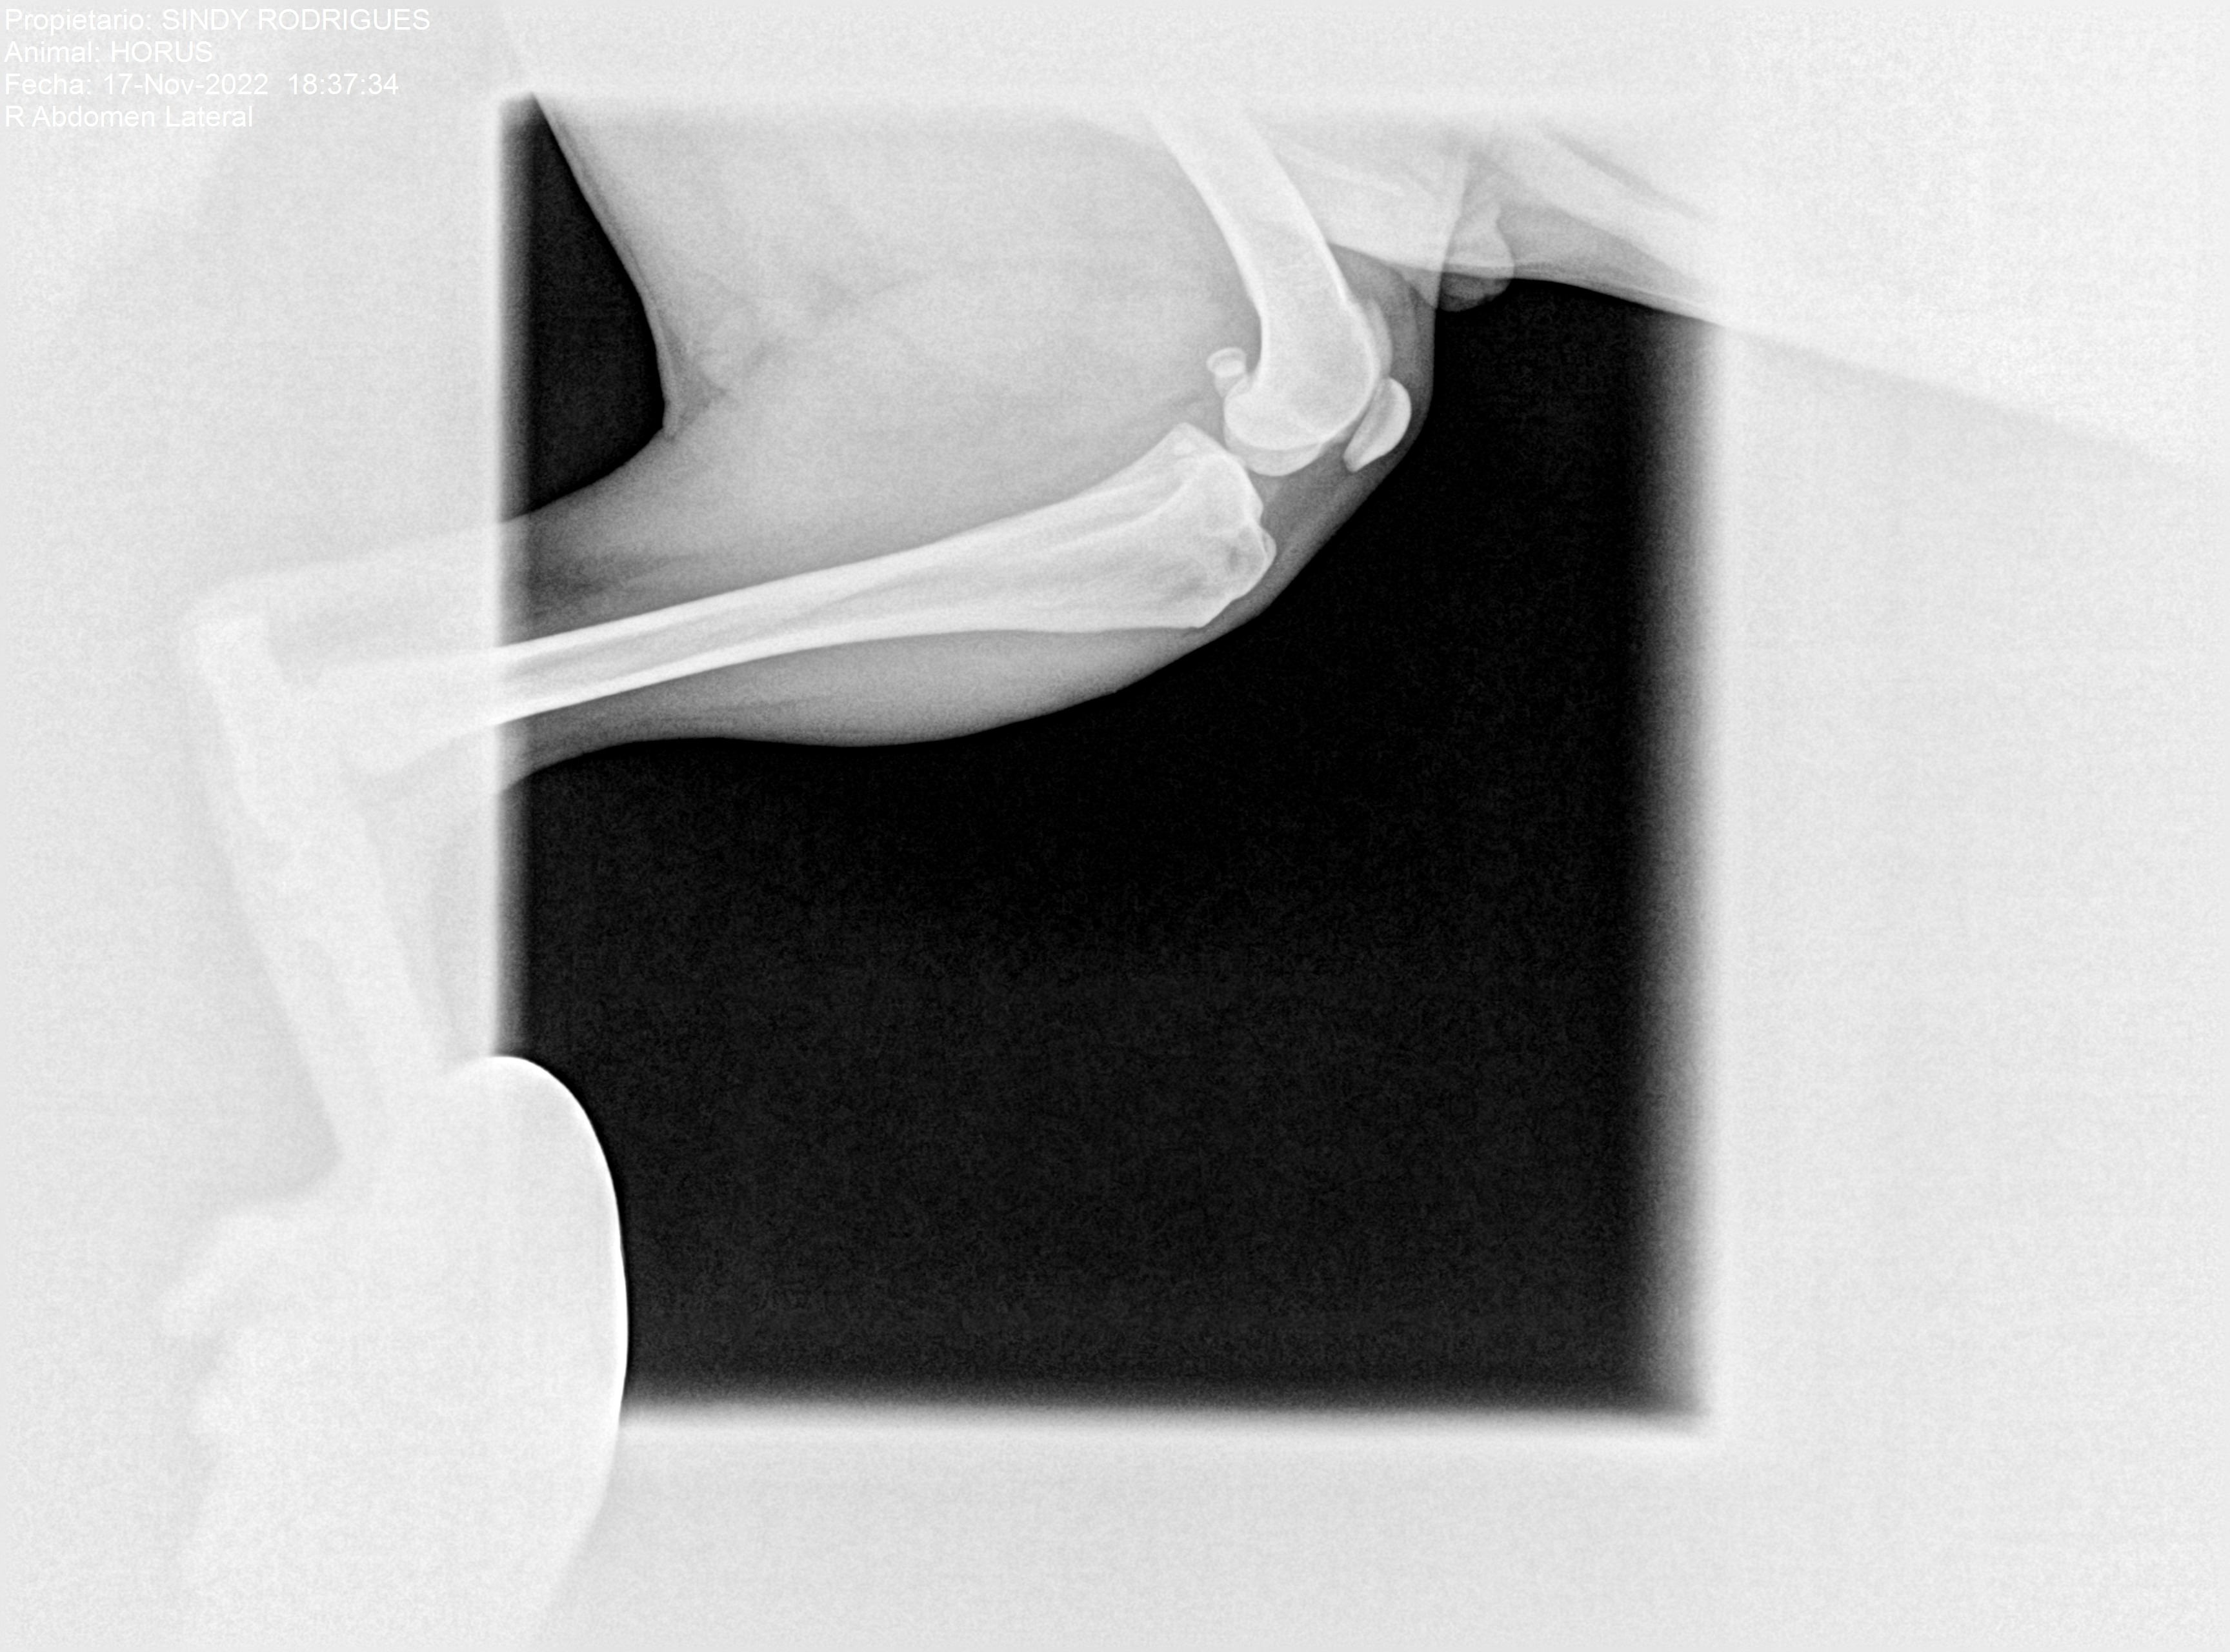

Hola me llamo Horus, he sufrido una ruptura de ligamento cruzado de mi patita izquierda y necesito operarme cuanto antes para no forzar mi otra patita y que no me pase igual, y estoy buscando echar una patita a mis papis para poder hacerlo cuanto antes, gracias a todos a los de buena voluntad.